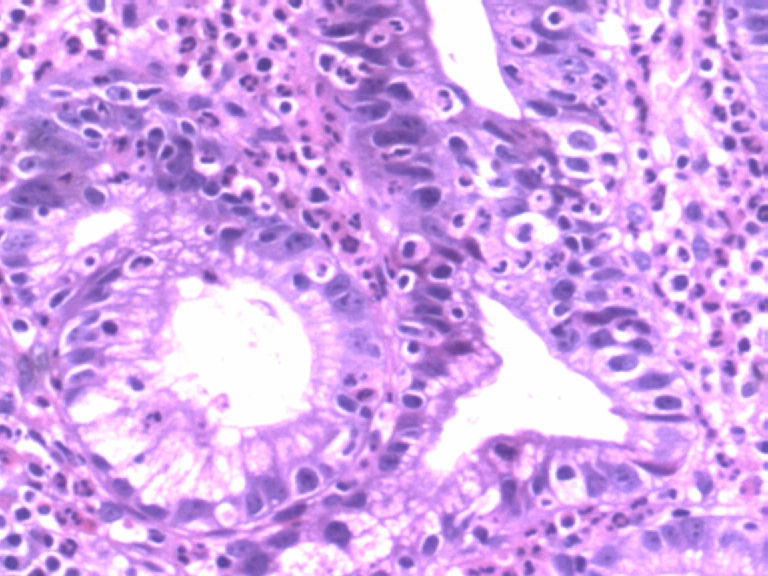

男,50岁,胃镜活检食管下段溃疡组织3块。

• 胃镜活检食管下段溃疡组织3块图1

图1

从图片看,应该是贲门部位的组织,显示急性炎症改变,腺体结构稍有不规则,可能为炎性刺激所致,总之未见肿瘤性病变。

图示急性炎症,炎症累及上皮,腺细胞反应性增生。

腺体有轻度异型,未见粘膜下浸润,应报“低级别上皮内瘤变”。建议重取材或密切随访。